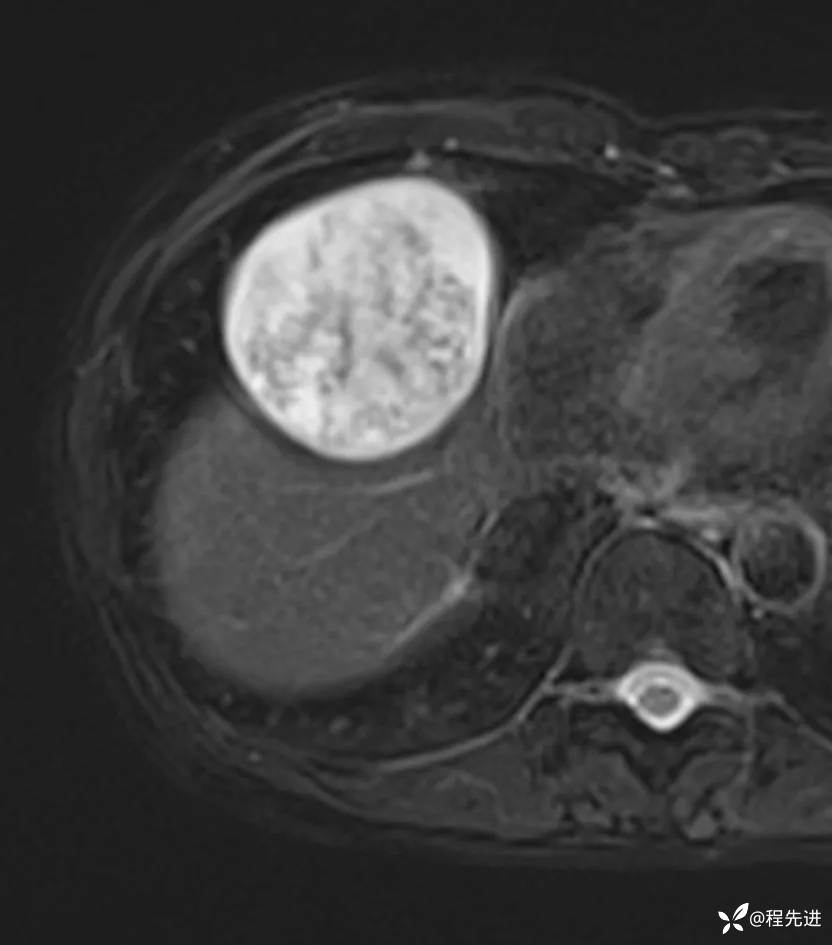

MRI平扫+增强: